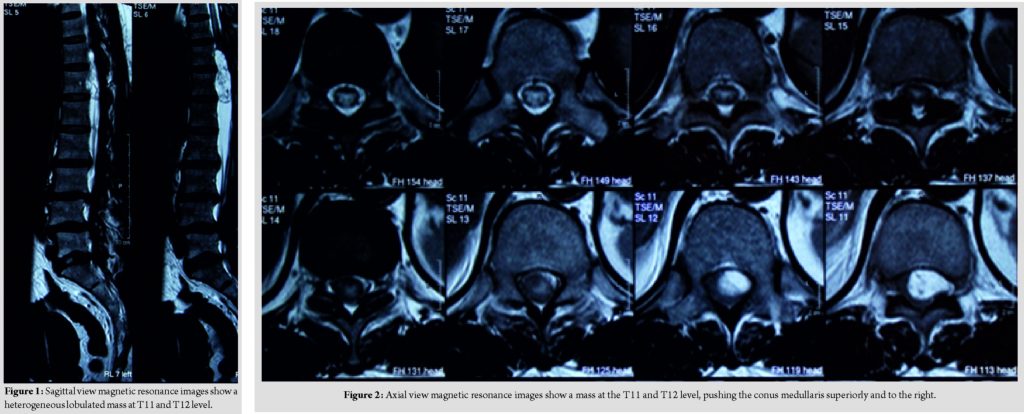

A 57-year-old female lady presented with complaint of sudden onset of urinary incontinence for 3 days duration. Further, history taking reveals that she has been having radiculopathy pain and bilateral lower limb weakness for a year duration. Clinical examination reveals that bilateral lower limb hypotonia, bilateral lower limb motor power of Medical Research Council (MRC) Grade 2, and bilateral lower limb reflexes were absent and sensory reduced from T11 dermatome onward. Magnetic resonance imaging reveals a heterogeneous lobulated mass in the spinal canal at T11 and T12 level, compressing and displacing the conus medullary superiorly and to the right (Fig. 1 and 2).